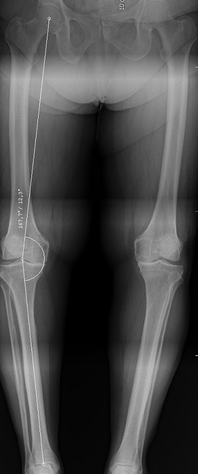

Genou